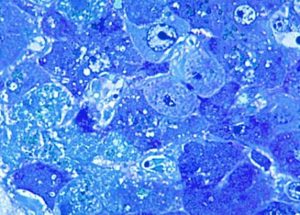

Ο ιός Έμπολα αρχικά προκαλεί ξαφνικό πυρετό, έντονη αδυναμία, μυϊκούς πόνους και πονόλαιμο.

Σταδιακά ο ασθενής κάνει εμετούς, έχει διάρροια και αιμορραγεί εξωτερικά και εσωτερικά.

Ο θάνατος συχνά επέρχεται από αφυδάτωση και πολυοργανική ανεπάρκεια.